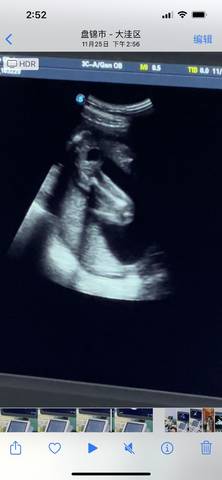

请问我这个是小男孩还是小女孩啊????有没有知道的啊 求告诉 谢谢啦

journal_insert_pic_1677719809journal_insert_pic_1677719813journal_insert_pic_1677719816

你好亲爱的,通过这个来判断男孩女孩是不太准确的哈。那么这个男孩女孩都是我们最爱的宝贝哈,我们要给他同等的关爱和呵护,也祝你可以如愿以偿,心想事成,祝你好运。

#我正在参加,超级妈妈大赛赢奖品 我猜是男宝,也要生后才能确定,宝妈也不要太在乎男女,也是你的宝宝,注意休息!

你好。我们是判断不了男宝宝跟女宝宝的,孕期定期检查,我觉得宝宝健康就好的。祝心想事成 。